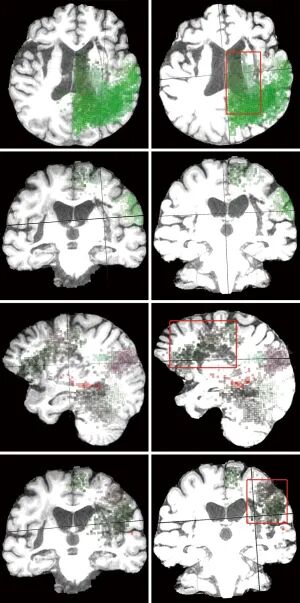

神经生理层面发现,训练后患者的EEG中央运动区PSD曲线更平滑,ERD现象更明显,提示皮层激活增强且向感觉运动皮层汇聚;MRI连接组学分析(以4号患者为例)发现,训练后其初级感觉运动皮层、运动前区、辅助运动区及额叶语言区的功能连接显著增强,运动与语言网络间出现新的连接,后部注意力网络也发生重塑,证实脑机接口训练可推动脑网络跨域协调。

患者4的感觉运动网络和语言网络相应皮层中像素的演化前后对比。与训练前的左列相比,右列显示出患者脑网络中与功能连接相对应的某些皮层像素颗粒的密度或范围(在红框内)在训练后显著增加。@Quant Imaging Med Surg